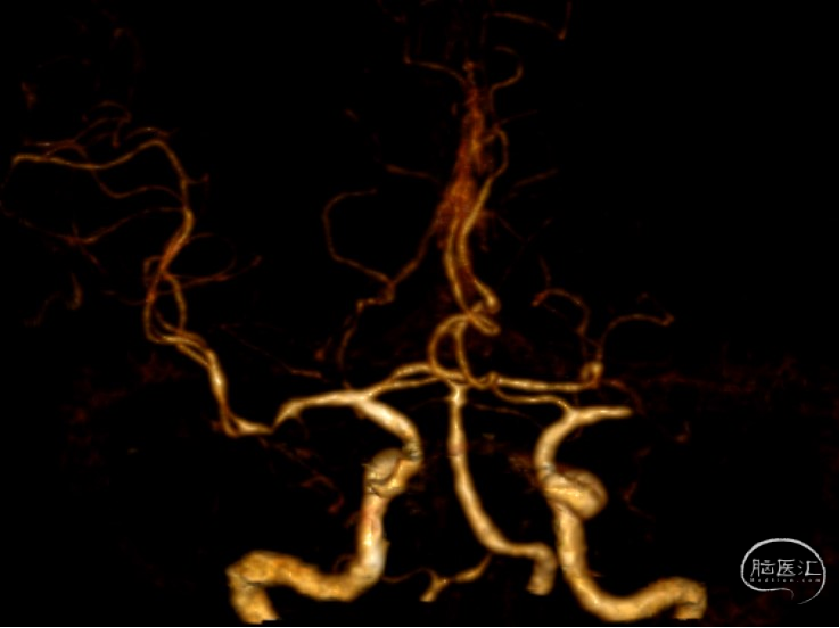

术后CTA:左侧大脑中动脉通畅,支架内无明显狭窄

再次给予Gateway球囊以6ATM压力缓慢扩张,并缓慢注射替罗非班5ml,观察20分钟,M1处血管毛糙,血管回弹明显,给予经微导管释放Neuroform Atlas 4.0mm×21mm支架满意。复查造影左侧大脑中动脉及大脑前动脉显影良好,mTICI3级,观察10分钟后,再次复查造影左侧大脑中动脉及大脑前动脉显影良好。行Dyna CT见未见明显出血灶。